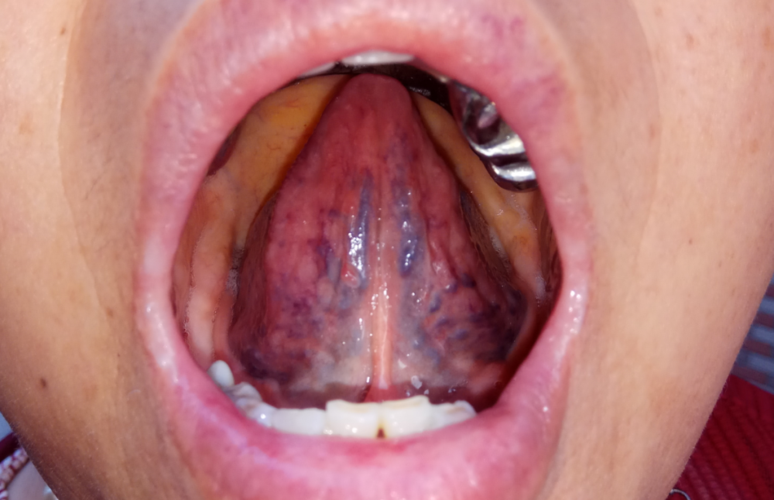

瘀紫舌:舌呈青紫色、暗紫色 , 大部分舌面还有瘀斑或瘀点 。 舌下络脉(特征明显)增粗、迂曲 , 或见屈曲成团 , 形成珠状瘀点 。

中医认为血瘀、血液循环不畅是肿瘤形成的重要病机 。 如果癌症患者有这种舌质 , 很容易发生转移 。

这是因为癌细胞转移的主要途径是血液 。 瘀紫舌的患者血液微循环障碍 , 血管壁容易破损 , 血液粘稠度高 , 癌细胞容易停留在血管壁受损的地方 , 借而生根发芽 , 生成转移病灶 。 同理 , 如果癌细胞是在血液里一直不停留的循环 , 就不容易转移 , 见淡红舌的癌症患者 。

中医认为瘀紫舌类患者 , 适合使用活血化瘀的办法改善 , 会对肿瘤病情会有帮助 。